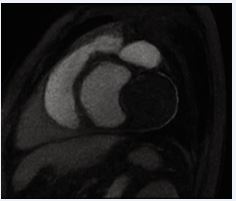

A 49-year-old male presented with complaints of intermittent palpitations for three years, increasing on exertion and associated with sweating. Clinical evaluation revealed atrial fibrillation with a controlled ventricular rate. Baseline echocardiography demonstrated a large mass in the interatrial septum measuring approximately 5.2 × 3.0 cm, suggestive of a cystic lesion with internal septations. Transesophageal Echocardiography (TEE) confirmed a large mass arising near the non-coronary sinus of Valsalva, raising suspicion of aneurysm with internal thrombus. Coronary angiography showed mild coronary artery disease. Cardiac MRI demonstrated an aneurysmal dilatation of the non-coronary cusp of the aortic sinus measuring 4.3 × 3.1 cm with eccentric mural thrombus, causing compression on the left atrium. No myocardial edema, perfusion defect, or late gadolinium enhancement was noted. CT coronary angiography further delineated a saccular aneurysm from the non-coronary sinus measuring 3.8 × 3.8 × 5.6 cm with non-enhancing thrombus, indenting the left atrium and right pulmonary vein. Calcified plaques causing mild luminal narrowing were noted in the left main coronary artery and left anterior descending artery. The total calcium score was 420. The cardiothoracic surgeon had assessed the operative risk to be significantly high in view of the patient’s very low body weight (40 kg), raising concerns regarding perioperative morbidity, hemodynamic instability, and postoperative recovery. These factors were clearly explained, and although surgery was advised, the patient declined the procedure after understanding the associated risks. In view of the high surgical risk and the patient’s informed refusal, we adopted a conservative management strategy. The patient was managed with rate control for atrial fibrillation and remains stable on follow-up (Figures 1-3).

Figure 1 Transthoracic Echocardiography showing large mass occupying the LA.